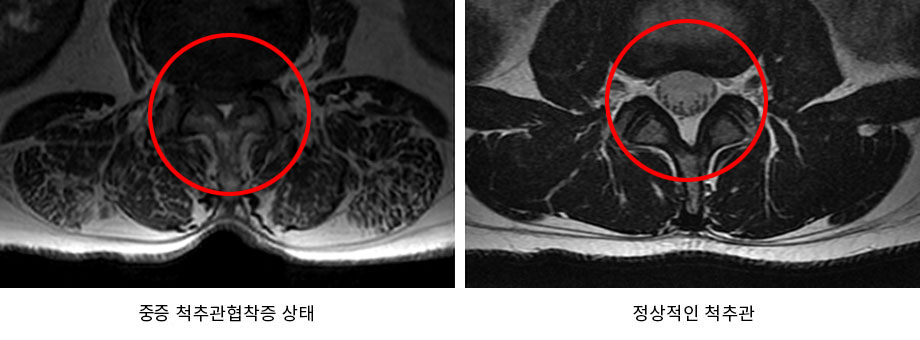

나이가 들면 우리의 몸도 같이 나이가 들게 됩니다. 우리 몸을 지탱해주는 척추 또한 나이를 먹으면서 퇴행되어 기능이 떨어지고, 약해지게 됩니다. 이러한 퇴행으로 인해 발생하는 대표적인 척추질환이 척추협착증입니다. 척추협착증은 척추를 둘러싸고 있는 근육과 인대가 퇴행되어 제 기능을 하지 못하게 되면서 척추관 내 황색인대가 비정상적으로 부풀어 오르게 됩니다. 척추관 내 황색인대가 부풀어 오름에 따라 척추관의 공간이 줄어들게 되면서 신경을 압박하게 되는데, 그로 인해 통증이 발생하는 질환입니다.

척추관 내 황색인대가 부풀어 오르는 이유는 우리 몸을 지탱하기 위해서입니다. 퇴행이 진행되면 척추를 비롯하여 척추 주변의 근육과 인대, 디스크 등도 퇴행이 되면서 기능이 떨어지고, 약해지게 됩니다. 척추를 지탱하는 근육과 인대, 디스크 등의 구조물들이 약해지게 되면 우리 몸은 어떻게든지 이를 지탱하기 위해 노력을 하게 되는데, 이 과정에서 황색인대의 몸집이 굵어지고, 단단해지면서 척추관을 좁아지게 만듭니다.